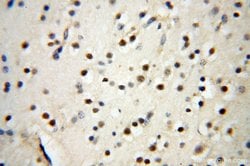

| Immunohistochemistry (Paraffin) | |

| Human, Mouse, Rat | |